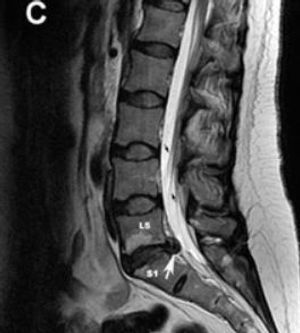

Would you consider oral steroids for a patient with acute radiculopathy due to a herniated disc? What's the clinical evidence of benefit?